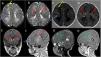

Presentamos un neonato a término en el que se realizó una ecografía torácica a pie de cama por dificultad respiratoria. El plano transversal mediante sonda lineal permite descartar neumotórax2, y, en este paciente, reveló varias imágenes hiperecogénicas bien delimitadas de hasta 2cm limitadas al miocardio (fig. 1, Supl). El parénquima pulmonar presentó un patrón intersticial con gradiente y línea pleural fina con deslizamiento, compatible con taquipnea transitoria (soporte respiratorio durante 48 h). La ecocardiografía corroboró el diagnóstico de túberes cardiacos y la resonancia magnética craneal evidenció túberes y nódulos subependimarios (criterios mayores), líneas de migración radial, nódulos subependimarios y quistes en la sustancia blanca (fig. 2) que, junto con el estudio genético, diagnosticaron al paciente de esclerosis tuberosa tipo II de Bourneville (gen TSC2).

Ecografía torácica a pie de cama. Sonda lineal. A) Plano transversal en la línea intermamilar. Se observa el esternón (*) y los tumores (túbers) incluidos en el miocardio (homogéneos, hiperecogénicos, x). Contrasta su aspecto con la menor ecogenicidad del miocardio (+). B) Plano longitudinal izquierdo: arco anterior de las costillas (*), túbers (x), mediastino (+).